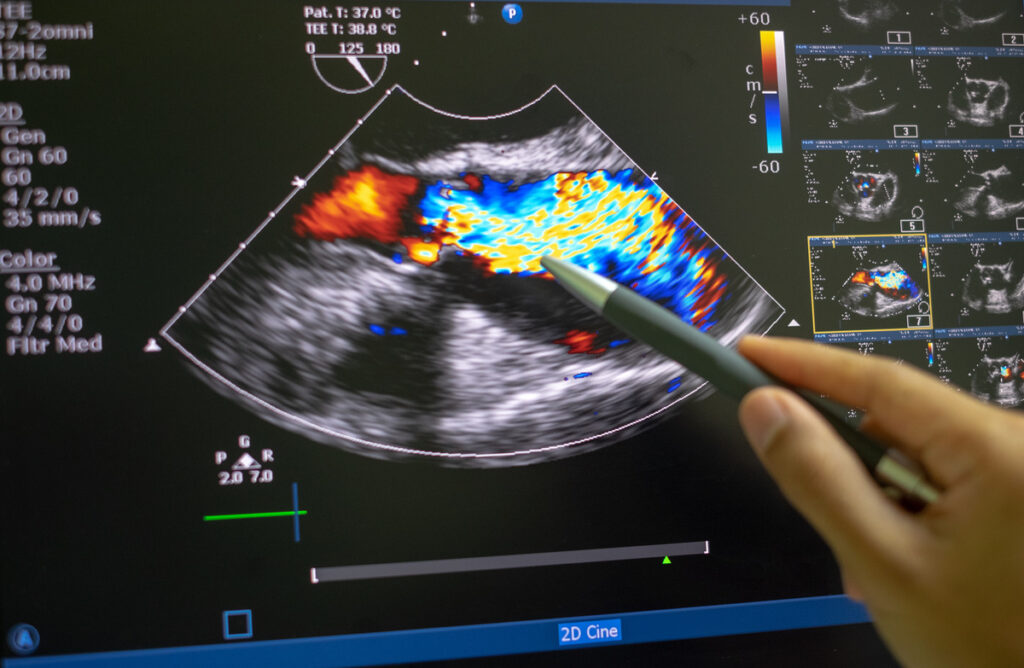

Especializada em oferecer cursos que atendem às diversas demandas da ultrassonografia, a instituição oferece programas de pós-graduação em Ultrassonografia Geral, Ginecologia e Obstetrícia, além de cursos de extensão em ultrassonografia para Mapeamento de Endometriose, Musculoesquelética, Dopplervelocimetria Vascular Periférica e Abdominal. Também são oferecidos cursos complementares e de aperfeiçoamento.

A ECUS é detentora de um corpo docente altamente preparado e disponível para proporcionar uma excelente aprendizagem. Contamos com especialistas renomados e qualificados em diversas áreas, como radiologia, ultrassonografia, ginecologia e obstetrícia. Além disso, nossa instituição possui uma estrutura física moderna, com salas de exames totalmente equipadas com aparelhos de última geração, especialmente planejadas para o ensino. Também dispomos de consultórios de alto padrão e uma equipe de apoio treinada para fornecer o suporte necessário.